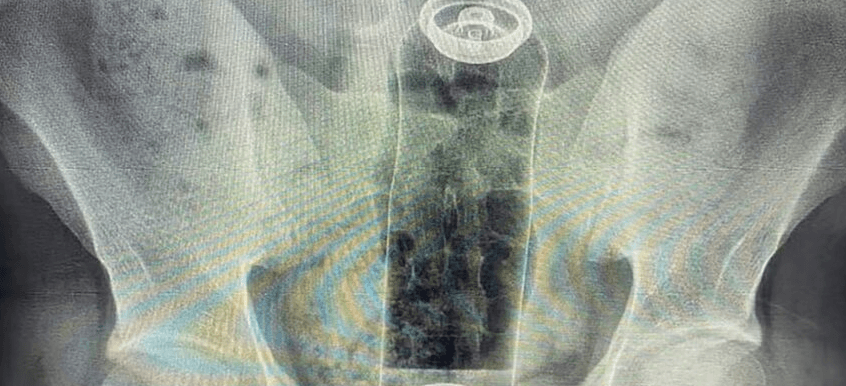

An x-ray image shows the deodorant stuffed in the bum, undated. A 19-year-old patient had inserted the item during a sexual game. Note: Private photo. (Newsflash)

A 19-year-old man had to be rushed to hospital after a deodorant container became stuck inside his rectum and could not be removed.

The patient, who was not named, was admitted to hospital in Sao Paulo, Brazil, with intense pain and abdominal discomfort after he inserted the deodorant during a "sexual game", local media reported on 26th January.

According to colorectal surgeon Daniel Brosco, the object moved further up and got lodged in the patient's rectum.